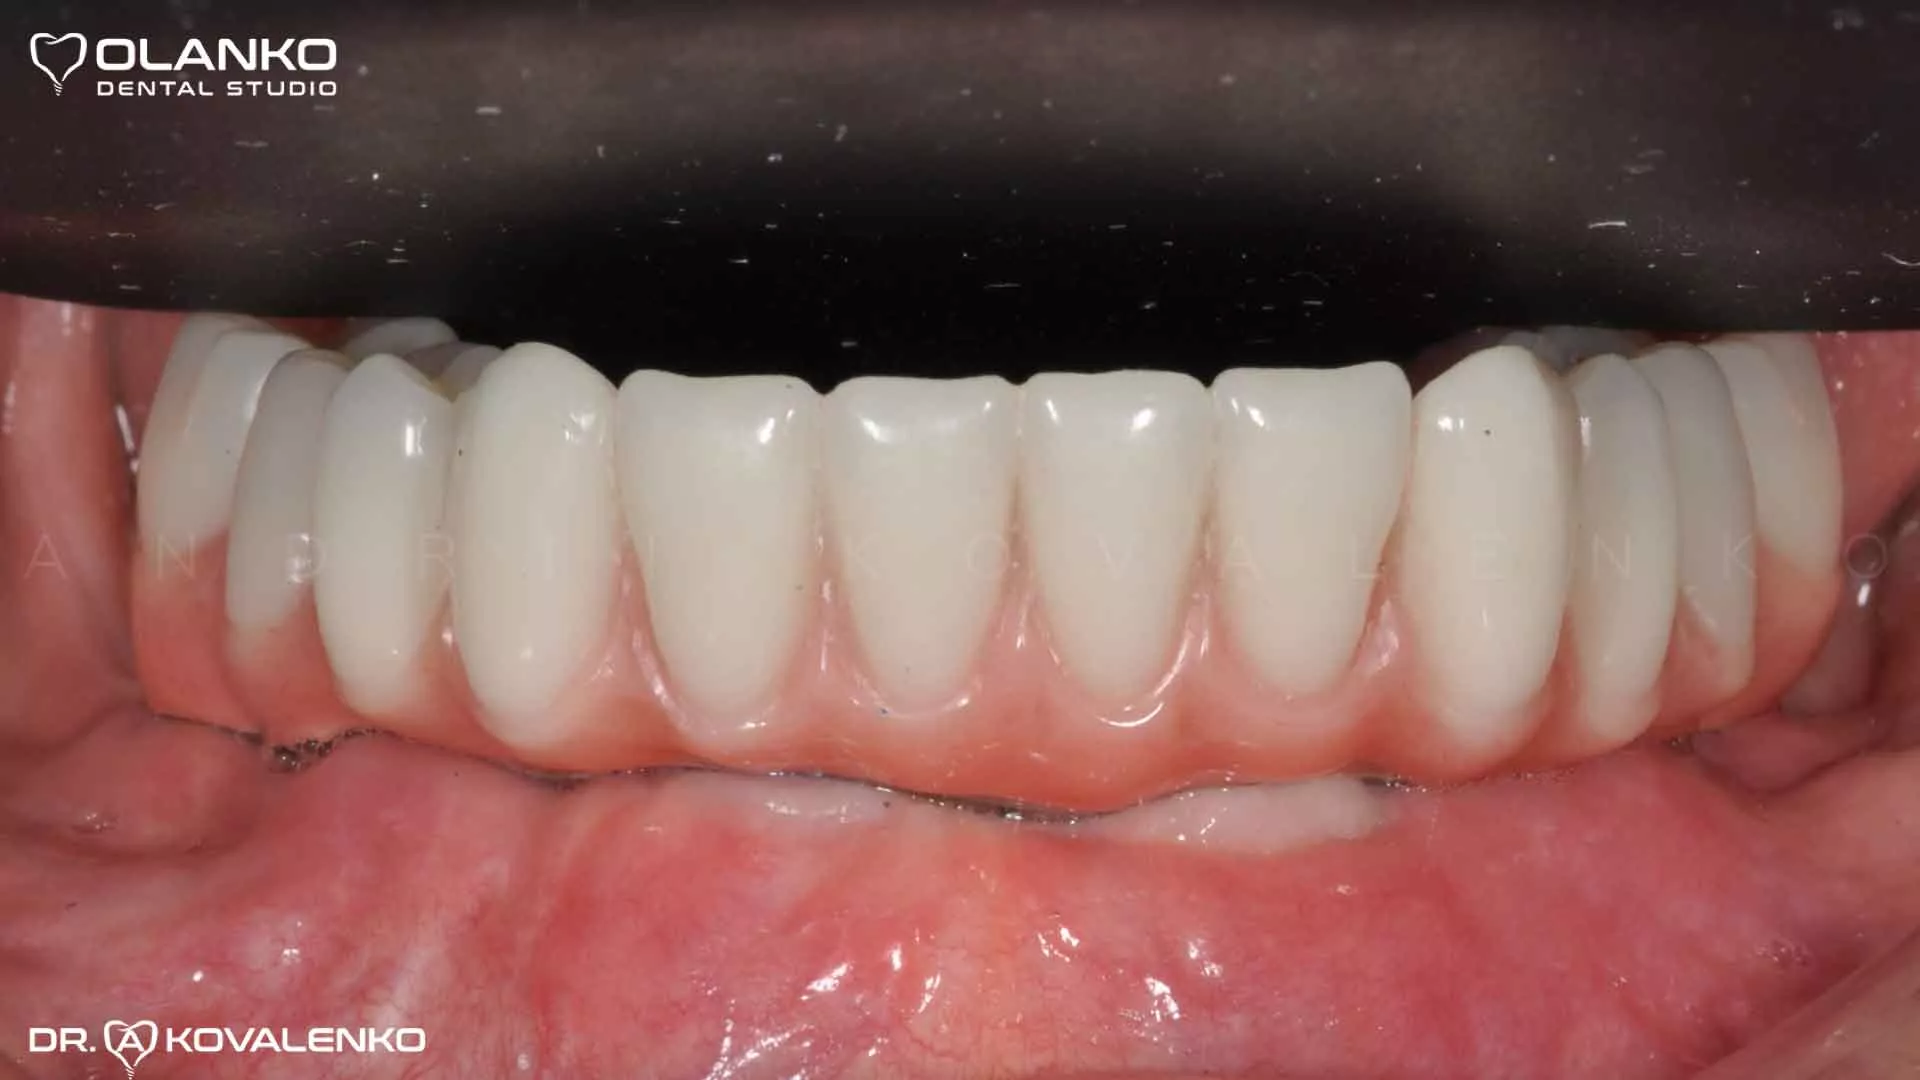

Пример протезирования по технологии All on 4 на беззубой нижней челюсти

Фото после установки и приживления имплантов

Импланты Nobel система номер 1 в мире

Фото после установки зубного протеза с опрой на 4 имплантата